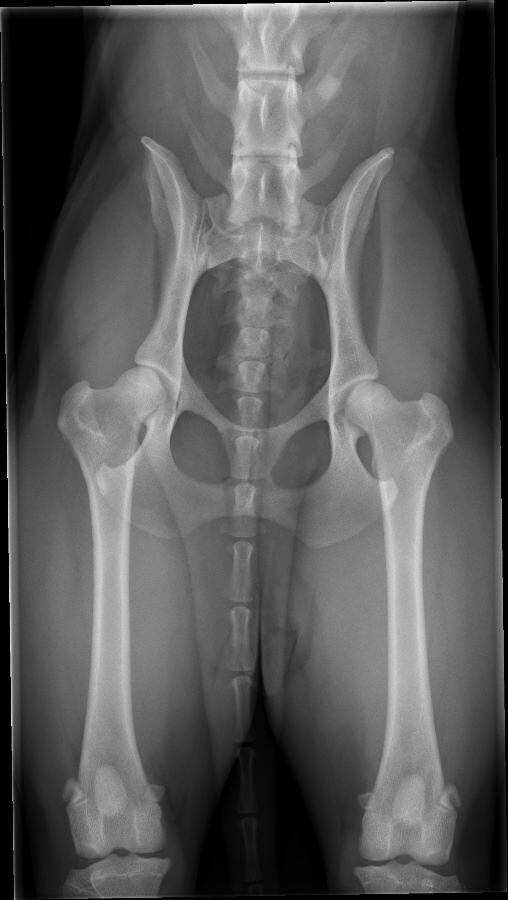

Uitslag heupen Mayla

Mayla 4 september 2019 heupen HD A